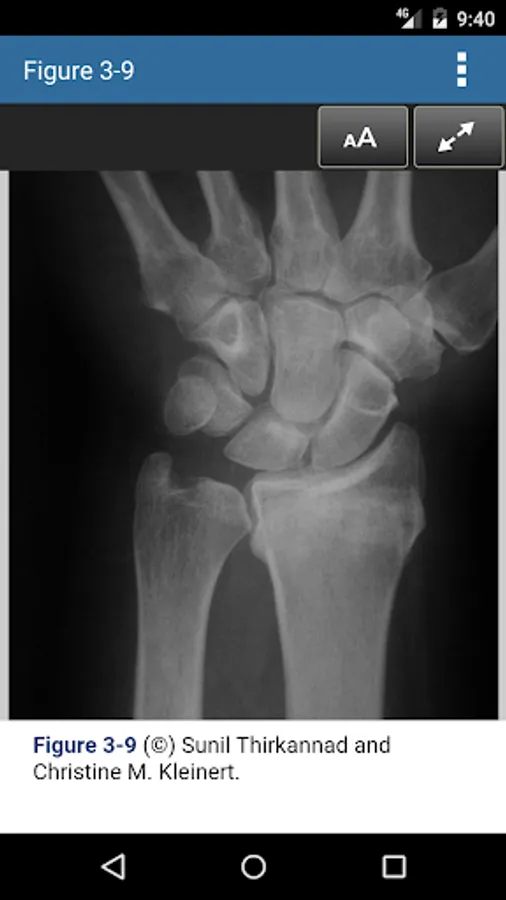

• Color photographs and illustrations to complement the text